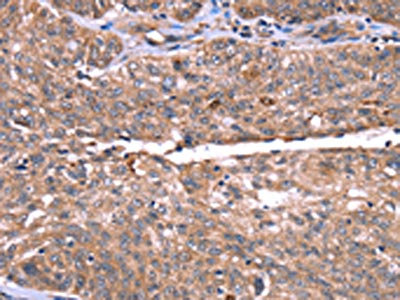

The image on the left is immunohistochemistry of paraffin-embedded Human breast cancer tissue using CSB-PA181107(HRG Antibody) at dilution 1/50, on the right is treated with synthetic peptide. (Original magnification: ×200)

The image on the left is immunohistochemistry of paraffin-embedded Human ovarian cancer tissue using CSB-PA181107(HRG Antibody) at dilution 1/50, on the right is treated with synthetic peptide. (Original magnification: ×200)